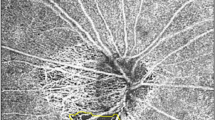

Methods The association between fundus pulsation amplitude as assessed with laser interferometry and pulse amplitude (PA) and pulsatile ocular blood flow (POBF) as assessed with pneumotonometry was investigated in 28 healthy subjects. Additionally, we investigated the distribution of fundus pulsation amplitude (FPA) in a region of -15° to + 15° around the macula (n = 18) and the influence of accommodation paralysis with cyclopentolate on FPA (n = 10).

Results There was a high association between FPA and PA (r = 0.86, p < 0.001) and FPA and POBF (r = 0.70, p < 0.001). Fundus pulsations in the macula were significantly smaller than in the optic disc, but significantly larger than those in peripheral regions of the retina. Administration of cyclopentolate did not influence FPA.